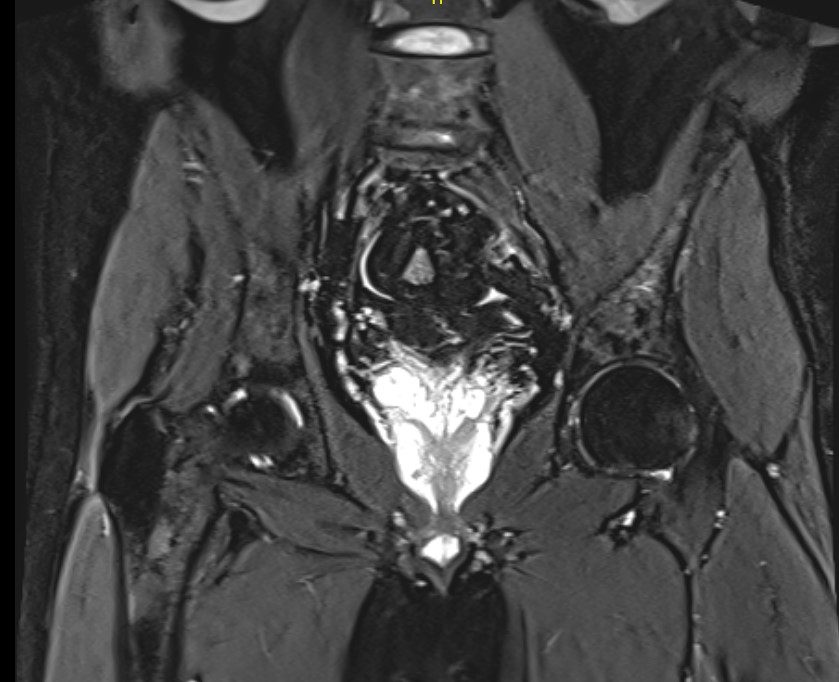

Sacrum

- irregular areas of bone destruction

- sacral expansion

- soft tissue mass

CT Scan / MRI

Useful to delineate tumour